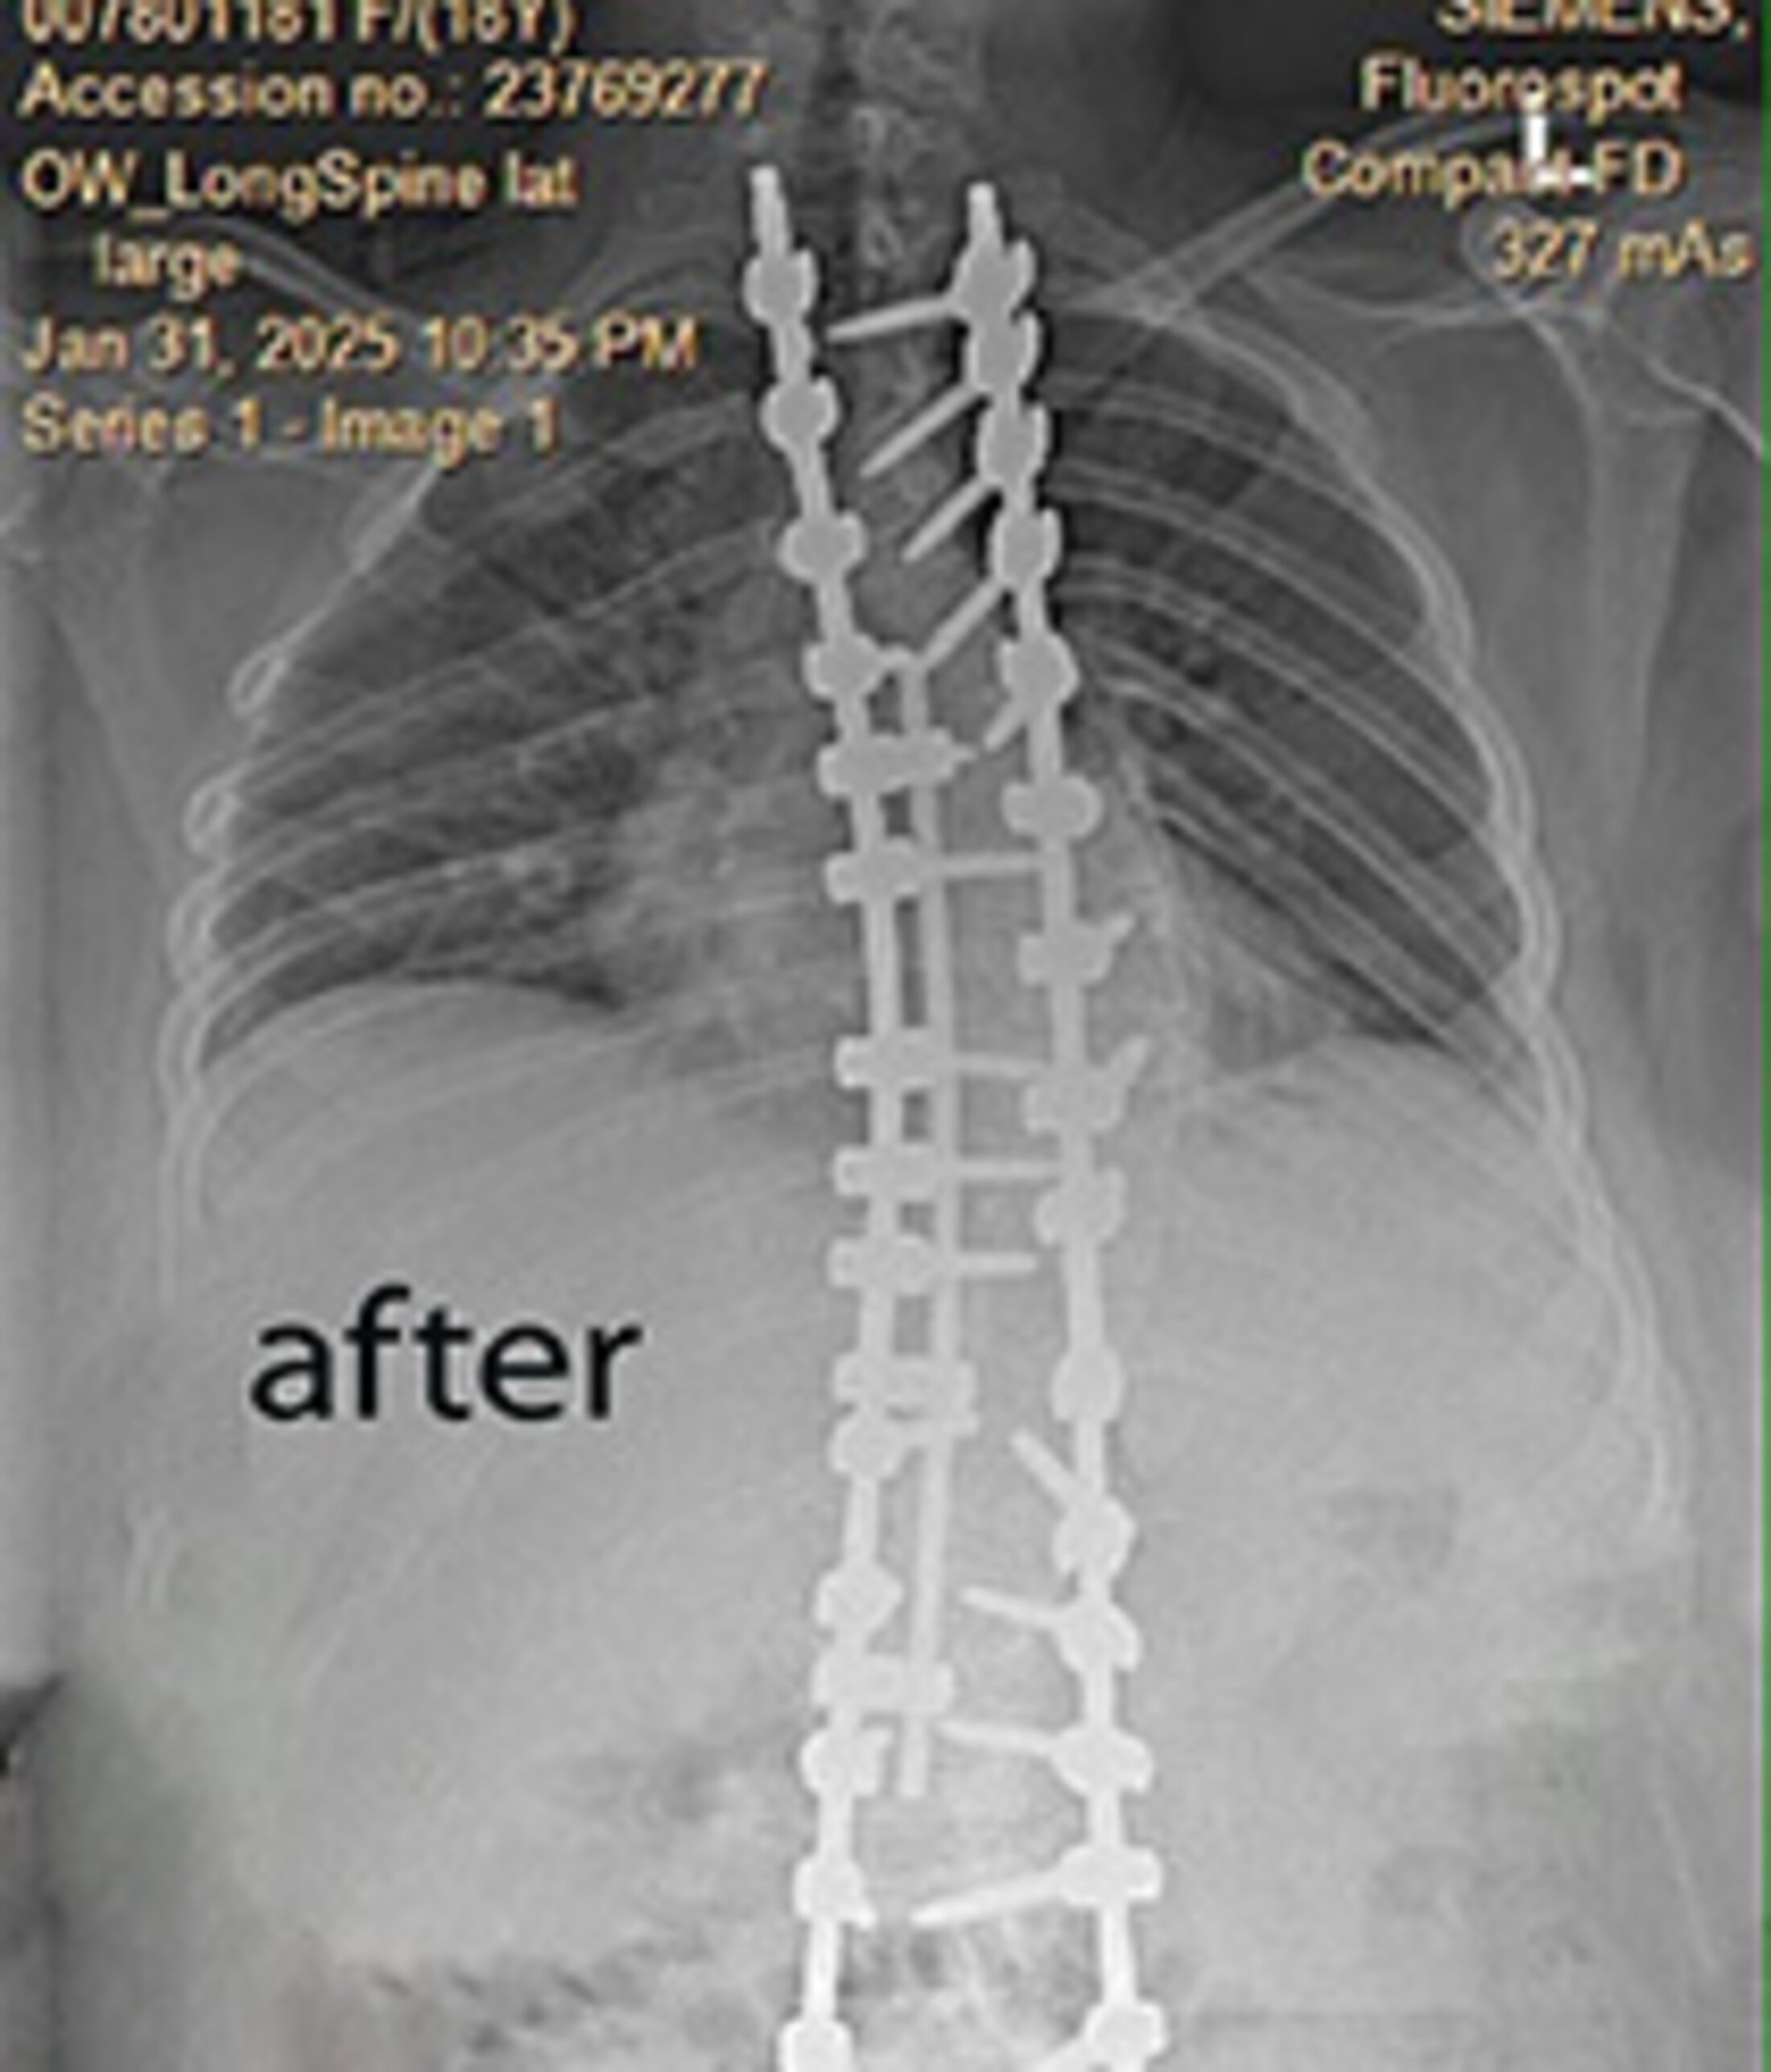

A post-surgery X-ray of Addy Powell's spine. Months later, and with the help of physical therapy, she returned to finish high school.

In January, Addy underwent a complex all-day surgery that straightened her spine and corrected her severe scoliosis. Performed by MUSC spinal surgeon Robert Ravinsky, M.D., the procedure saved her from possible paralysis by the age of 25. "My scoliosis was so bad that it was considered a spinal deformity," Addy said.

The next morning, she woke up in the intensive care unit. She said she was the youngest patient by far in the ICU and had tubes everywhere. Within hours, she was standing and walking.

Four days later, having received care from “the best nurses in the world,” as Addy put it, she was discharged. A week later, she walked half a mile around her neighborhood. And on March 17, she returned to school. In April, she resumed working as a barista at The Grind, although with modified hours. “The only thing I can’t do is take out the trash, but I’m not sad about that,” she said.

Instead, she’s focusing on all the good things she can do, like wear a dress with a zipper, show off her straight spine in a swimsuit and breathe deeply because her organs are no longer “squished.”